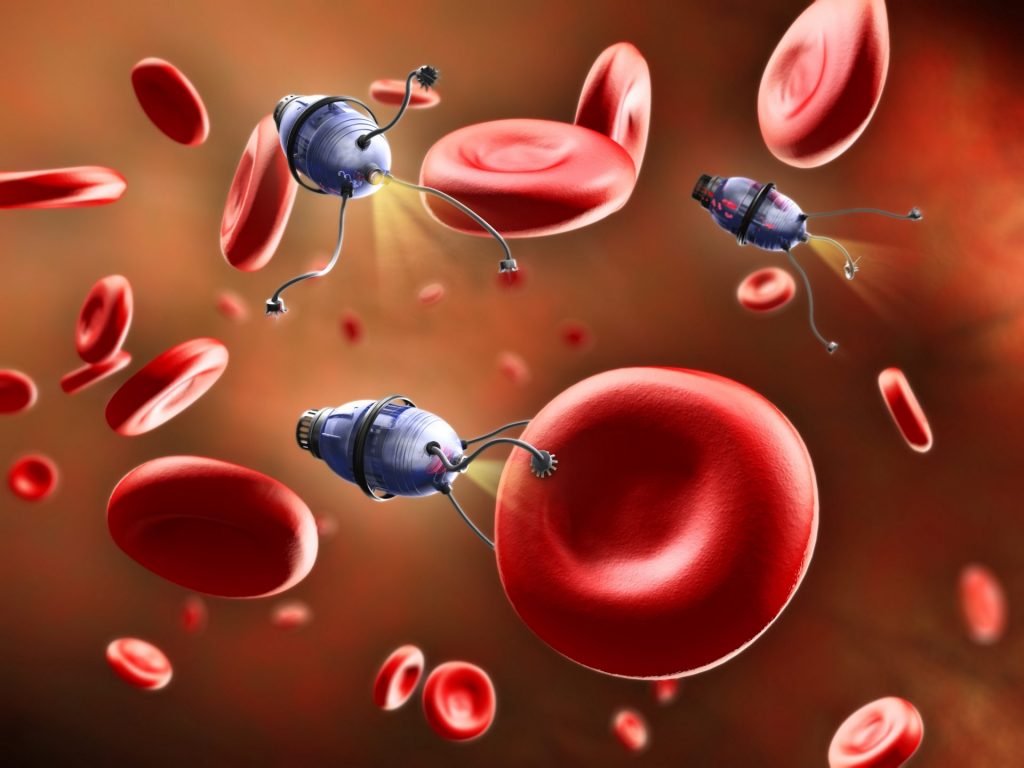

Xenobots have been created in labs back in 2020 from frogs’ stem cells to deliver medical payloads inside the human circulatory system, clean up the diseased arteries or even clean the ocean from plastics when produced in high droves and put into the ocean. They can even exhibit collective behavior in the presence of a swarm of other Xenobots and thus act as some sort of single being.

In the future, clinical applications such as targeted drug delivery Xenobots could be made from a human patient’s own cells, which would bypass the immune response challenges of other kinds of micro-robotic delivery systems. InO-Bot could be used to scrape plaque from arteries and with additional cell types and bioengineering, locate and treat disease. Aside from these immediate practical tasks, the Xenobots could help researchers to understand more about complex cellular behaviors and disease mechanisms.

Even if we controlled Xenobots at absolute precision, which we currently are not able to do. But that is a field at which thousands of researchers are looking currently, whether it’s for delivering nanobots to someone’s brain for enabling high-bandwidth brain-computer interfaces, or people modifying human cells to extend someone’s longevity.

Xenobots are not only for making useful machines. We can imagine programming Xenobots to go out into the environment and collect toxins and clean up, or, we can imagine Xenobots made of human cells that would go through our bodies and collect cancer cells or reshape arthritic joints.